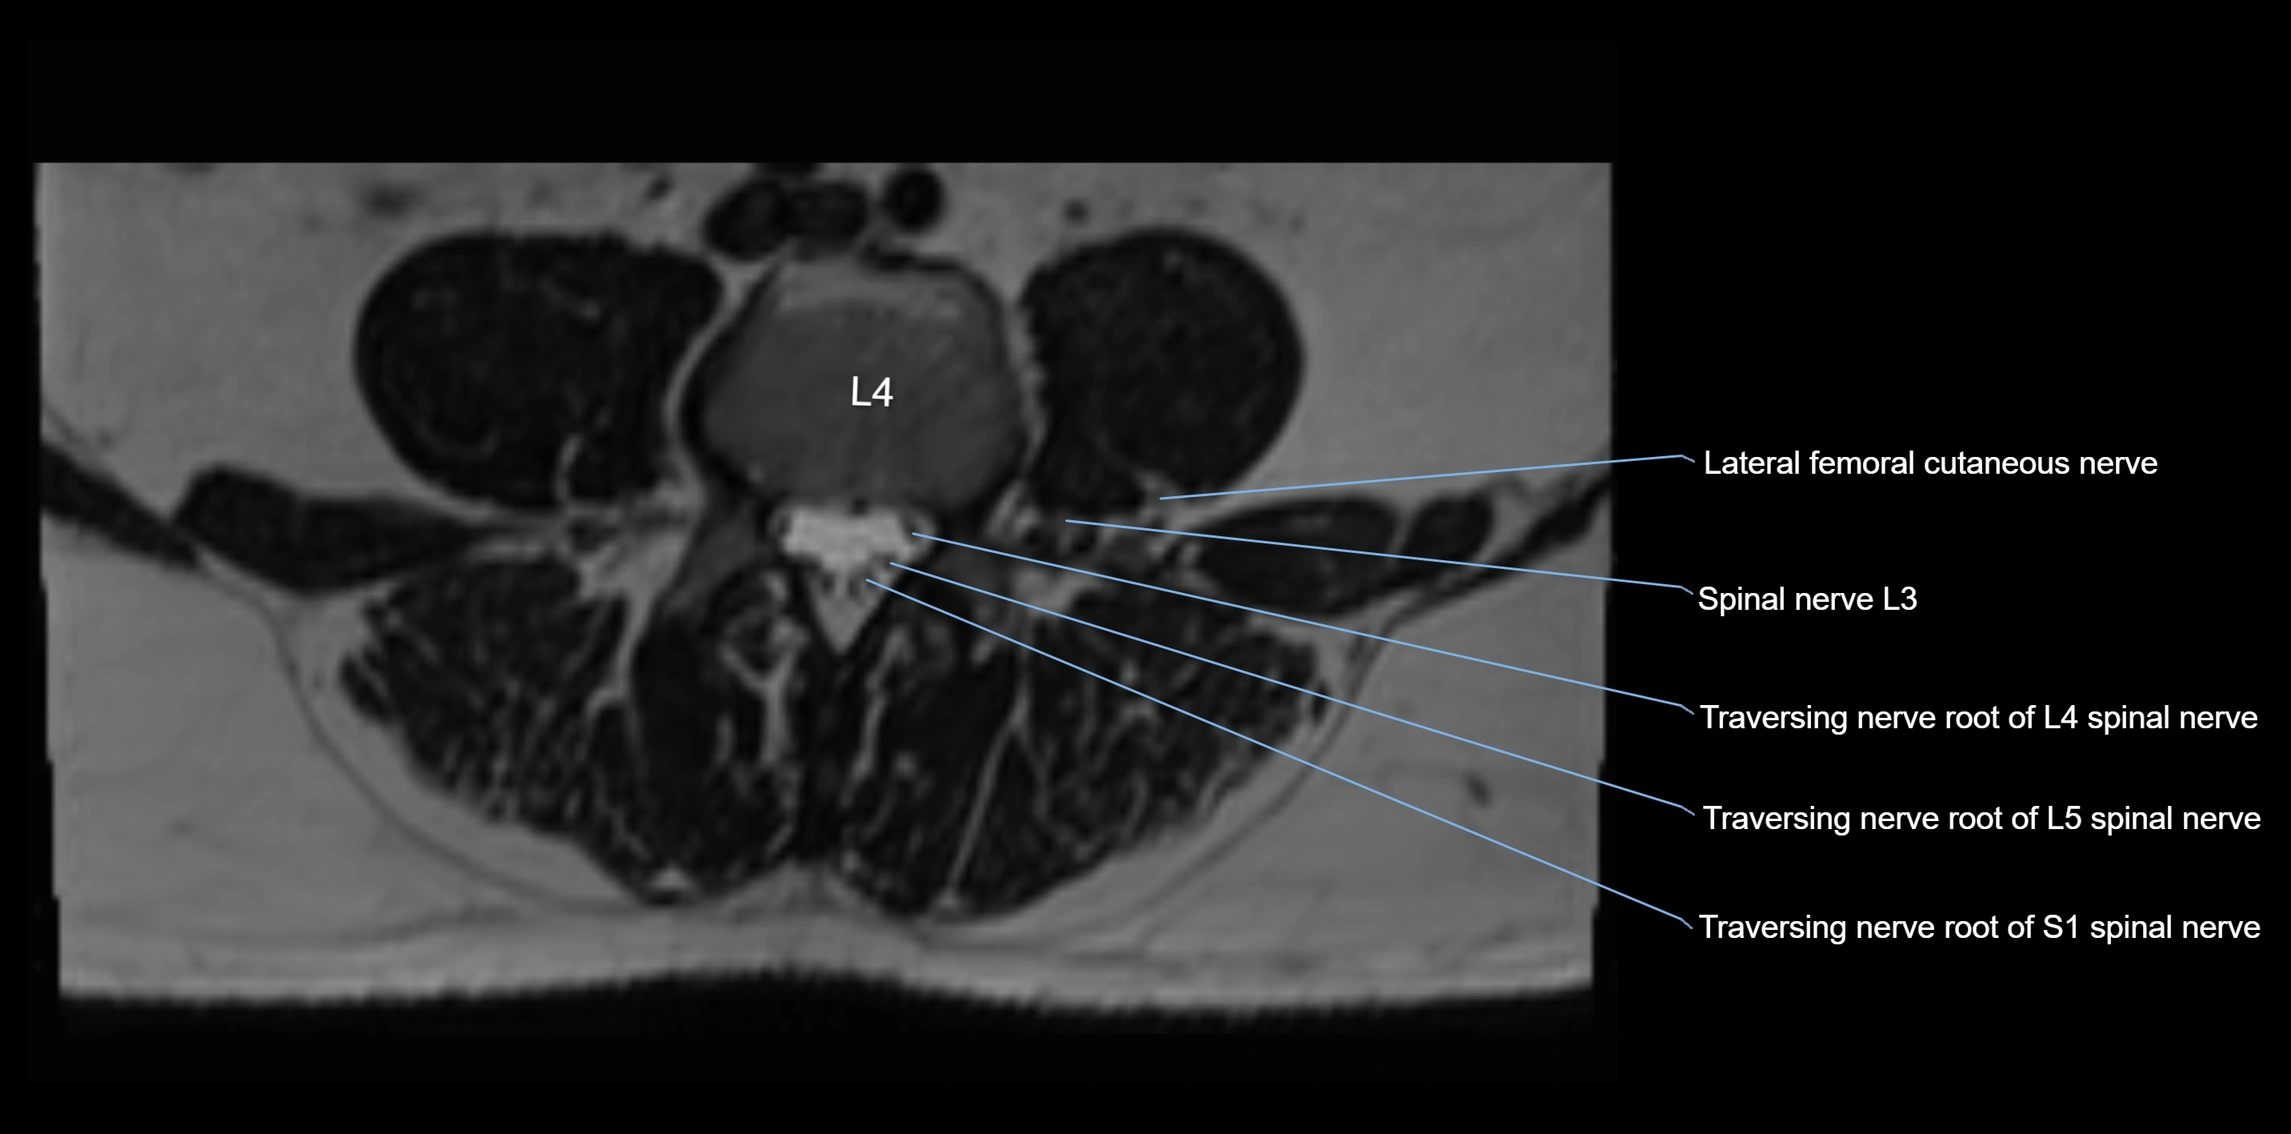

MRI Appearance

T1-weighted images:

• Nerve appears as a very thin low-to-intermediate signal intensity structure

• Surrounded by bright fat, aiding visualization

T2-weighted images:

• Nerve shows intermediate to mildly hyperintense signal compared to muscle

• Pathological involvement appears brighter

STIR (Short Tau Inversion Recovery):

• Normal nerve appears dark

• Inflamed or entrapped nerve appears bright hyperintense

T1 Fat-Sat Post-Contrast:

• Normal nerve enhances minimally

• Pathologic nerve (neuritis, entrapment, tumor infiltration) shows focal or diffuse enhancement

3D T2 SPACE / CISS:

• Nerve appears intermediate to mildly hyperintense compared to muscle

• Surrounded by bright fat or CSF, improving visualization

• Best sequence for mapping small pelvic nerves such as the anococcygeal